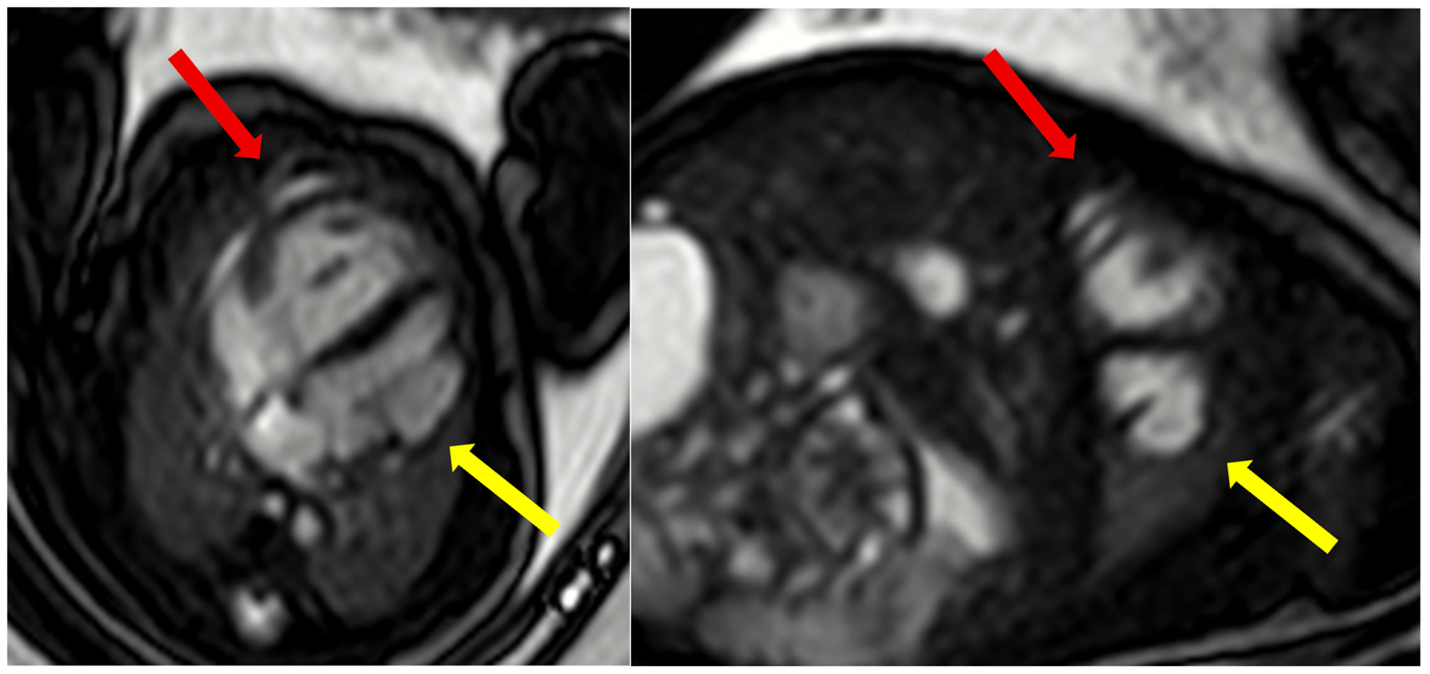

Figure 2: Fetal cardiac magnetic resonance (CMR) imaging in a 35 week fetus. Fetal Doppler-derived ECG gated balanced steady state free procession cine imaging in 4-chamber plane (left panel) shows a dilated coronary sinus with anomalous pulmonary venous drainage of at least three pulmonary veins draining into the coronary sinus (yellow arrow). Additionally, a large mid to apical left ventricular diverticulum was identified measuring 25 × 9 mm in diastole and 17 × 7 mm in systole (red arrow). Cine imaging on postnatal CMR (right panel) done in the first week of life with a comparative 4 chamber plane showing the left ventricular diverticulum (red arrow).